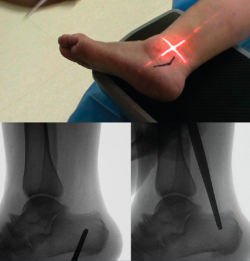

Osteosíntesis

Una vez comprobado el suficiente desplazamiento en la proyección axial del calcáneo, se fija la osteotomía con 2 agujas de Kirschner sobre las que se introducirán 2 tornillos canulados de un tamaño de entre 5,5 y 7 mm, y se verifica su correcta colocación en la visión lateral y axial fluoroscópica (Figura 9).

Figura 9. Imágenes fluoroscópicas de fijación de la osteotomía con agujas de Kirschner y tornillos canulados en anteroposterior y axial del calcáneo.